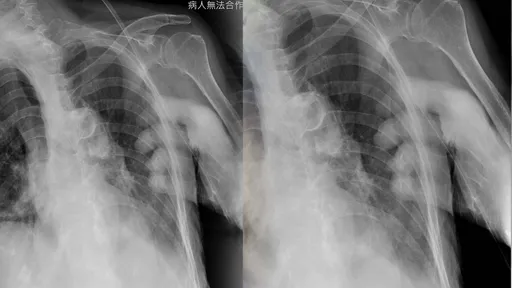

...總動員,共同投入防疫工作,其中,非常辛苦的就是醫事放射師,近距離藉醫學影像驗證病人的確診情況。 蔡...